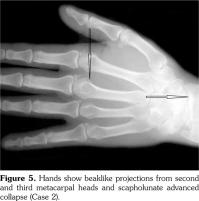

His hand X-rays showed hook like projections arising from radial aspect of second and third metacarpal heads with scapholunate advanced collapse and indentation of distal radius by the scaphoid bone. It also showed CC of the triangular fibrocartilage (Figure 6).